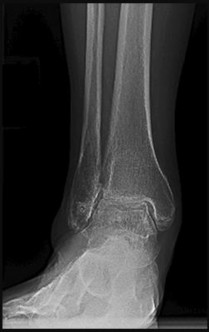

A 55-year-old patient with long-standing, poorly controlled diabetes mellitus presents with an acute, red, hot, and swollen right foot. Radiographs demonstrate extensive osteopenia, periarticular fragmentation, bony debris, and midfoot subluxation. According to the Eichenholtz classification of Charcot neuroarthropathy, which stage does this represent?

Correct Answer: Stage I (Development/Fragmentation)

Explanation:

The Eichenholtz classification describes the radiographic evolution of Charcot arthropathy. Stage I (Development or Fragmentation) is characterized by acute inflammation clinically, and radiographs showing osteopenia, periarticular fragmentation, subluxation/dislocation, and bony debris. Stage 0 lacks radiographic findings but has clinical swelling. Stage II (Coalescence) shows absorption of fine debris and early fusion. Stage III (Consolidation) shows remodeling and fixed deformity.